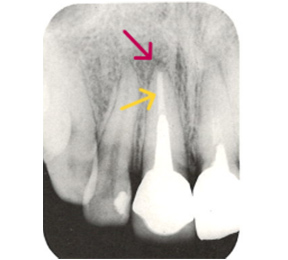

こちらのレントゲン写真を見てください。どちらかの歯医者さんで神経を取っています。根管に入れる薬は白く映ります。赤矢印部分です。一番右側が模式図ですが、青い部分が薬、根っこの先の赤点が化膿している部分です。

薬がほとんど入っていないのがわかります。黄矢印部分です。青矢印まで薬が入らないといけないのですが、全く入っていません。その結果、根っこの先が黒くなっています。膿が貯まって化膿すると黒く写ってくるのです。

別な歯科医院で治してもらいました。薬が根の先まで入っているのがわかります(黄矢印)。 根尖の黒い影が消失しています(赤矢印)。骨が再生すると白く写るようになります。

ガッタパーチャポイントは、理想的には歯根(シコン)の先ピッタリが良いと言われています。

しかし先ほど説明したように根管(コンカン)の形態は非常に複雑怪奇です。なので一概にピッタリが良いと限らないケースもあります。

ここでは一応、根尖(コンセン)付近が良いということにしておきましょう。

上の図にあるように神経の管に入れる薬が根尖(コンセン)まで入っていなかったり、途中までしか入っていなかったり、薬がスカスカだったりするとその空間にばい菌が繁殖して感染を起こします。

そうすると神経を取ったはずなのに、その後歯ぐきが腫れて痛くなるのです。

この根っこの病気を根尖性歯周炎というのです。そしてこの根尖性歯周炎を治すことを感染根管治療と言います。

大事な話なのでもう一度説明します。

①の写真はどちらかの歯医者さんで神経を取ってもらったレントゲン写真です。根っこの中に薬が全く入っていません。

②の模式図で青く描かれている部分が薬です。

根の先を見ると小豆ぐらいの大きさの黒い影が見えます。根の中でばい菌が繫殖し感染を起こすとこのような黒い影ができます。黒い影の部分は膿(ウミ)が貯まっています。こうなると腫れて痛みが出てくるのです。

③、④の写真はそれを治した後のレントゲン写真とその模式図です。白く映っている薬が根の先まできちんと入っているのが確認できます。そして根の先にあった黒い影が消えているのが分かります。根の先の炎症が治って、骨が再生すると白く映るのです。

実はこのケース、歯医者さんの神経を取る治療でこのような根っこの病気になってしまったのです。そこでこの患者さんは神経を取った歯医者さんではなく、別の歯医者さんに受診して、根っこの治療をして治したのです。